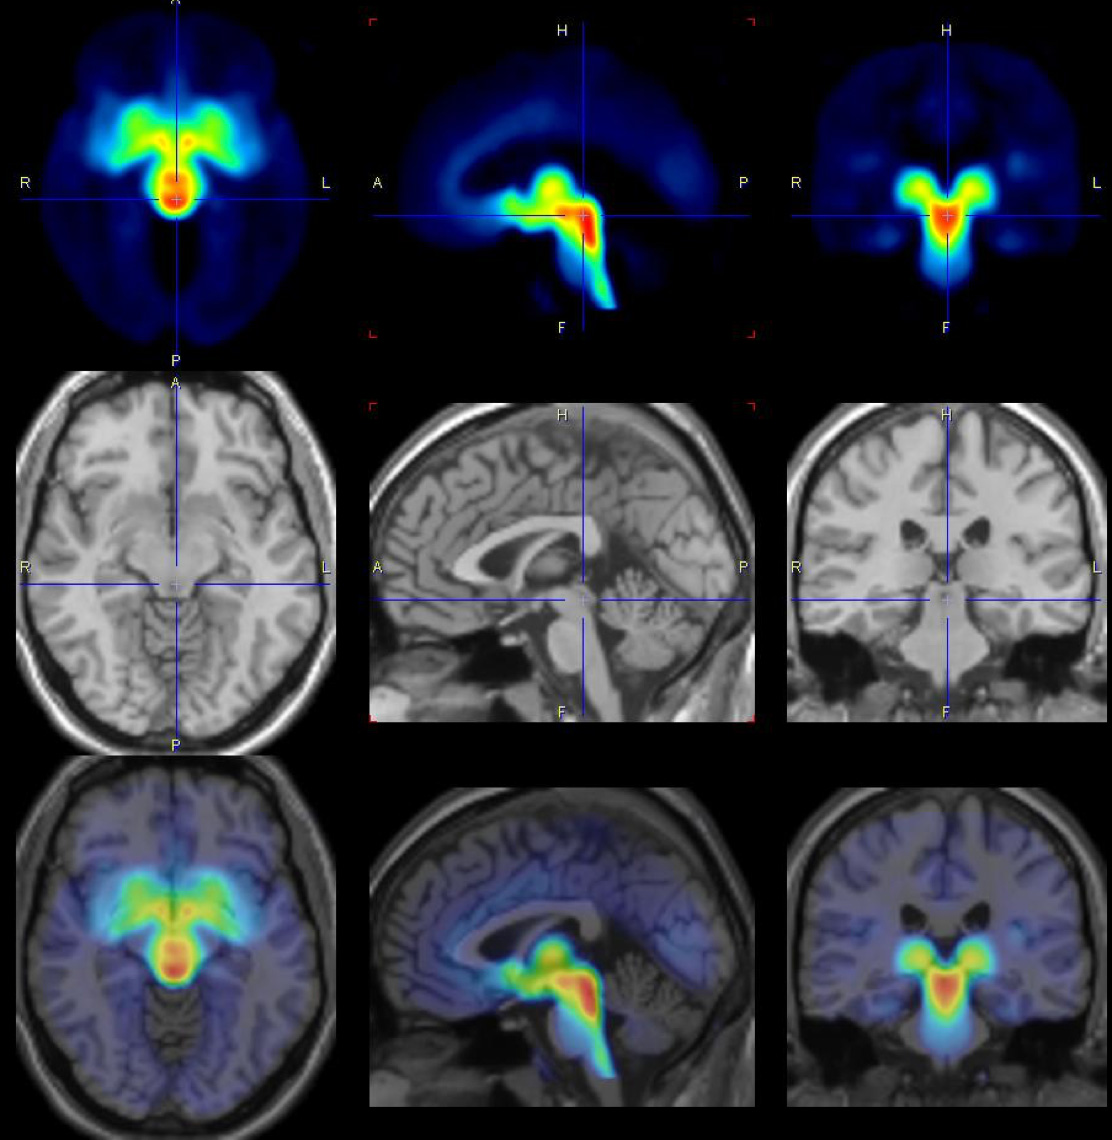

"We examined 30 female patients and 29 healthy study participants over several menstrual cycles and took images of the brain with positron emission tomography (PET) at different cycle times. We found that shortly before menstrual onset, the serotonin-transporter in the brain is increased and thus promotes a synaptic loss of this neurotransmitter, which can explain the affective symptoms in the affected women. This finding is surprising because it was previously thought that serotonin transporter density could not change in a short time span of two weeks - normally this is considered to be an individual trait with only minor changes over the period of 10 years is assumed."

The scientists took images of the womens’ brain with positron emission tomography (PET) at different cycle times.